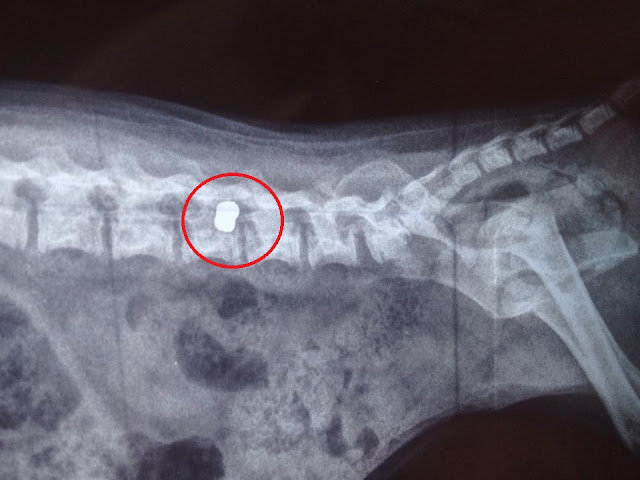

Το κουτάβι τότε μεταφέρθηκε στην κτηνιατρική κλινική του Κυριάκου Αγαθαγγελίδη στη Θεσσαλονίκη ο οποίος και υπέγραψε τη γνωμάτευση αναφορικά με την κατάσταση του ζώου και την αίτια που έμεινε παράλυτο καθώς η ακτινογραφία δείχνει το σφαιρίδιο του αεροβόλου σφηνωμένο στην σπονδυλική στήλη του κουταβιού.